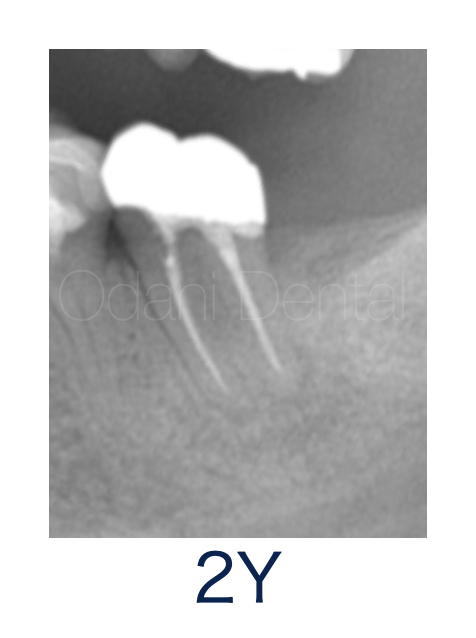

術後2年経過時のレントゲンですが、経過良好です。治療終了後2年が経過しましたが、痛みなく噛めるようになり、日常生活に支障なくお過ごしいただいています。あと一歩 遅かったら抜歯に至った可能性があったので、保存に成功してとても喜んでいただきました。